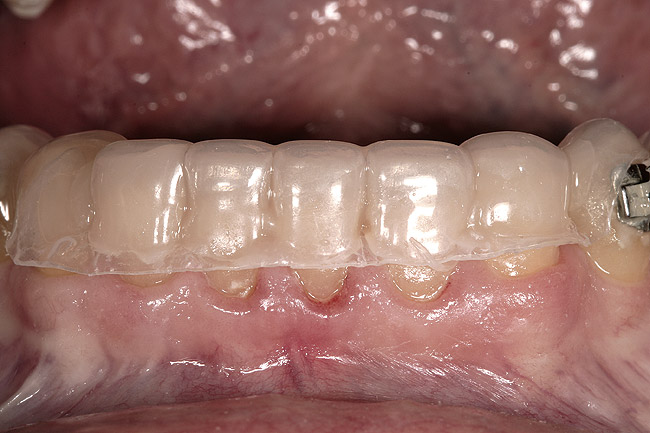

Figure 7  A full-arch temporary was placed to correctly identify an acceptable incisal edge position prior to surgery.

Figure 7